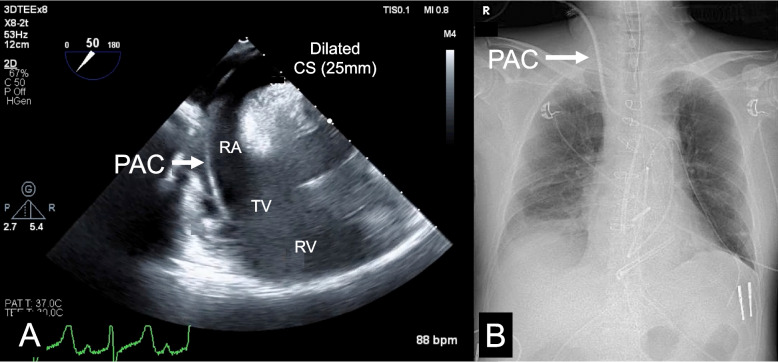

Pulmonary artery catheter insertion in a case with undiagnosed isolated persistent left superior vena cava.